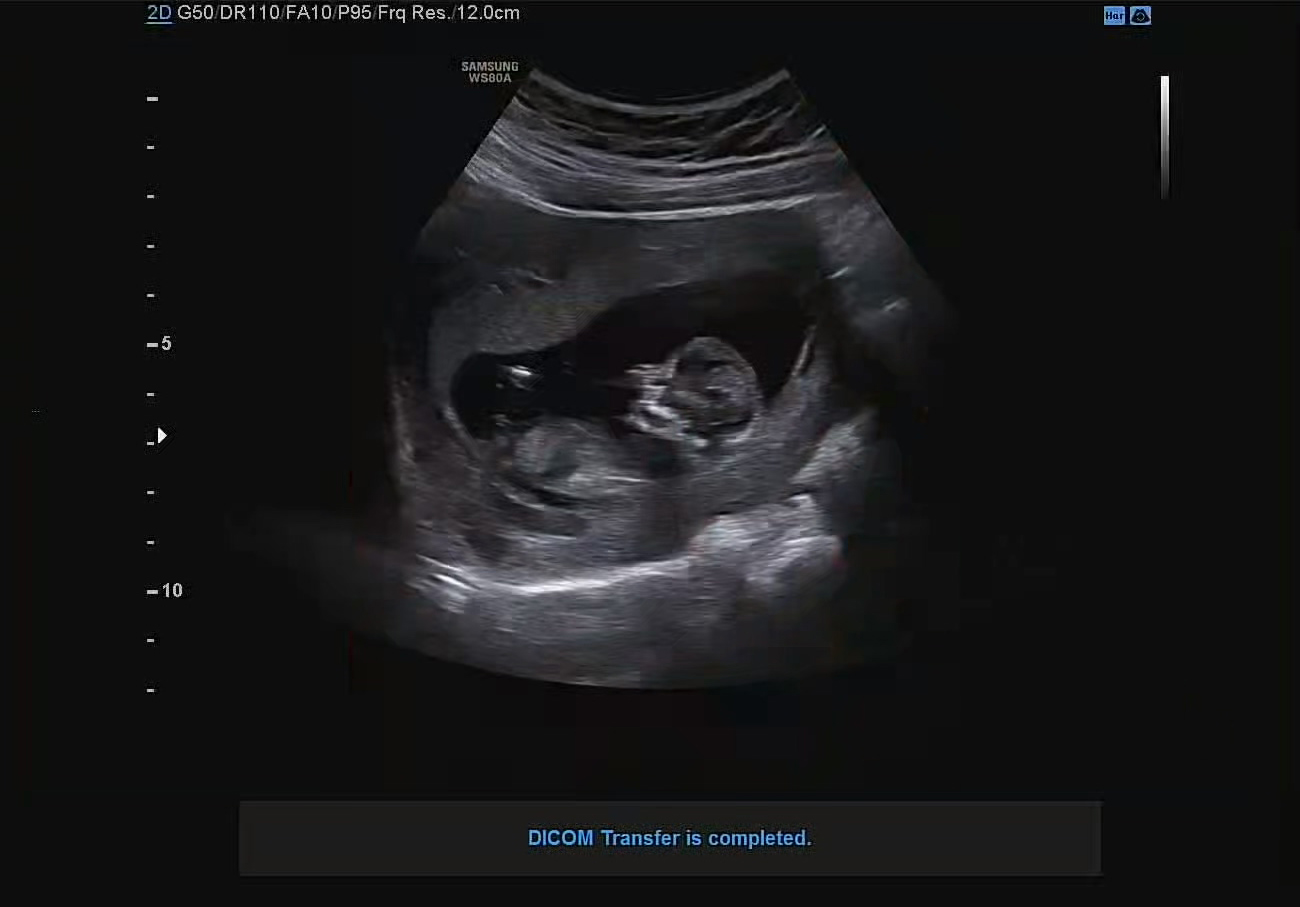

초음파 상이지만 확실히 9주 차 때보다 실루엣이 더 커지고 또렷해진 느낌이다. 특히나 얼굴에 보이는 골격이라고 해야 하나, 그런 디테일이 더 많아진 느낌적인 느낌.

까꿍이의 목 두께는 1.38mm, 코뼈도 2mm로 다행히 결과는 정상범위로 나왔다.

아이 크기는 5-6cm, 몸무게는 35~51g 정도로 크기는 라임 정도라고 할 수 있다. 아기의 골수에서 백혈구를 만들고 있고, 세균과 스스로 싸울 준비를 하고 있다고 한다.